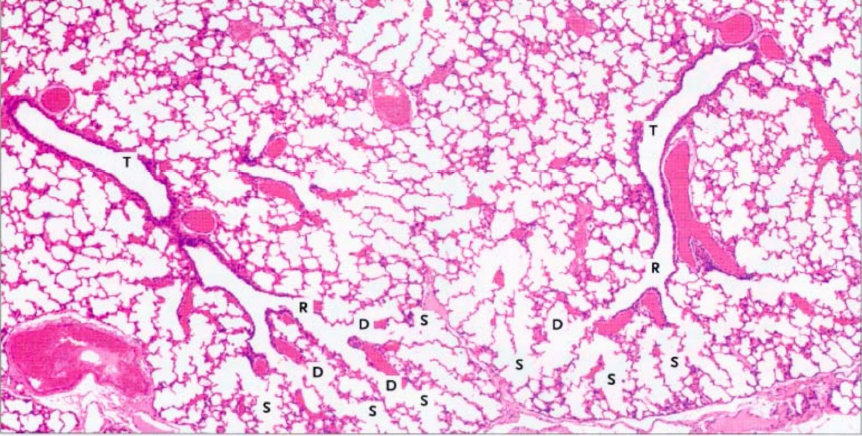

What structural changes occur at the intrapulmonary bronchi?

What is the differential between bronchus and bronchiole?

loss of cartilage

What is the structure of bronchioles?

What is the structure of the terminal bronchioles?

What is the structure of the respiratory bronchioles?

What is the structure of alveoli?